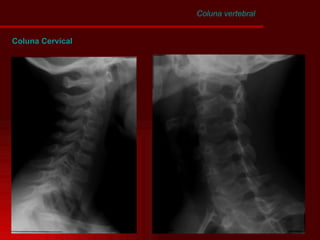

Coluna Cervical Coluna vertebral

Coluna vertebral Coluna Cervical